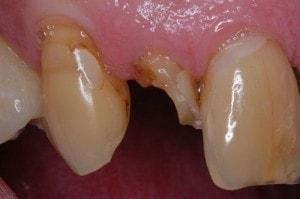

Carles removed

Enamel tapered on both preps. Enamel taper includes the entire labial of tooth #7. Many call this an apple core prep.

Pre-opt incisal view

-